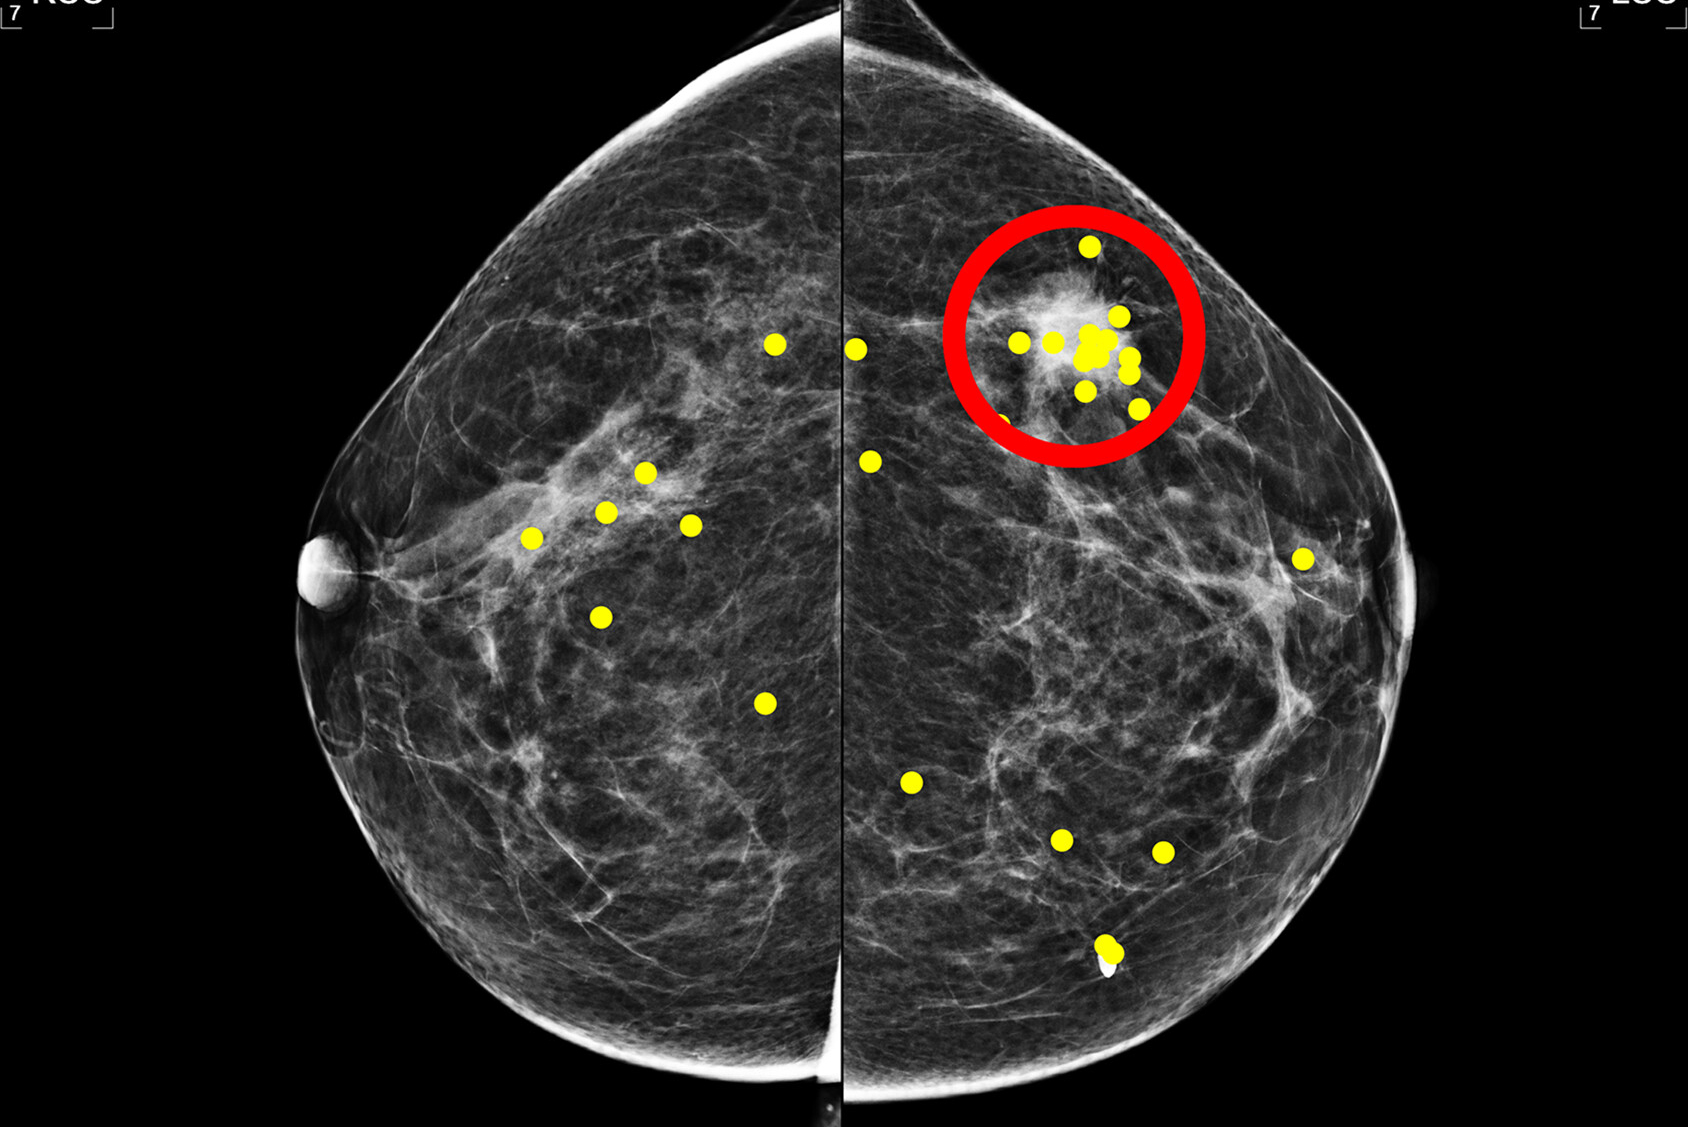

While screening mammography is the gold standard for early detection of breast cancer, proponents of biennial breast screening say that annual screening can lead to increased risks, including more false-positive cases that can lead to unnecessary additional imaging and biopsy.

Miglioretti and colleagues evaluated potential connections between screening mammography results and the probability of subsequent screening. They used data from 177 participating facilities from the Breast Cancer Surveillance Consortium (BCSC).

The final analysis included data collected between 2005 and 2017 from 3,529,825 screening mammograms. Of these, 3,184,482 were true-negative cases while 345,343 were false-positives. Mammography data came from 1,053,672 women aged 40 to 73 years. The women did not have a breast cancer diagnosis.